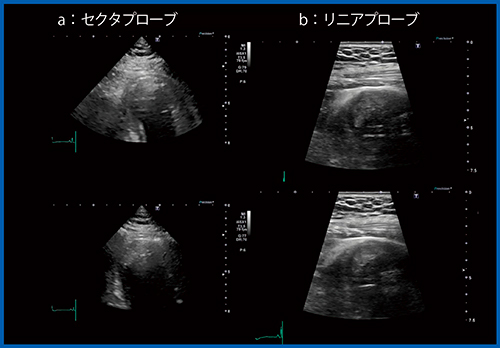

症例2は,50歳代,男性。左前下行枝の急性心筋梗塞(AMI)に対する経皮的冠動脈インターベンション(PCI)後2週間の症例である。Aplio i900にて,心尖部領域の広範囲に壁運動異常が認められ,同部位に壁在血栓を疑う像が確認できたが,自信を持って血栓と診断できない(図8 a)。このような時には,リニアプローブを用いることで,心尖部の壁の薄くなった領域と血栓の状態がより明確に判断できる(図8 b)。

図8 症例2:セクタおよびリニアプローブによる左室壁在血の描出

(AMI,PCI後2週間の症例)